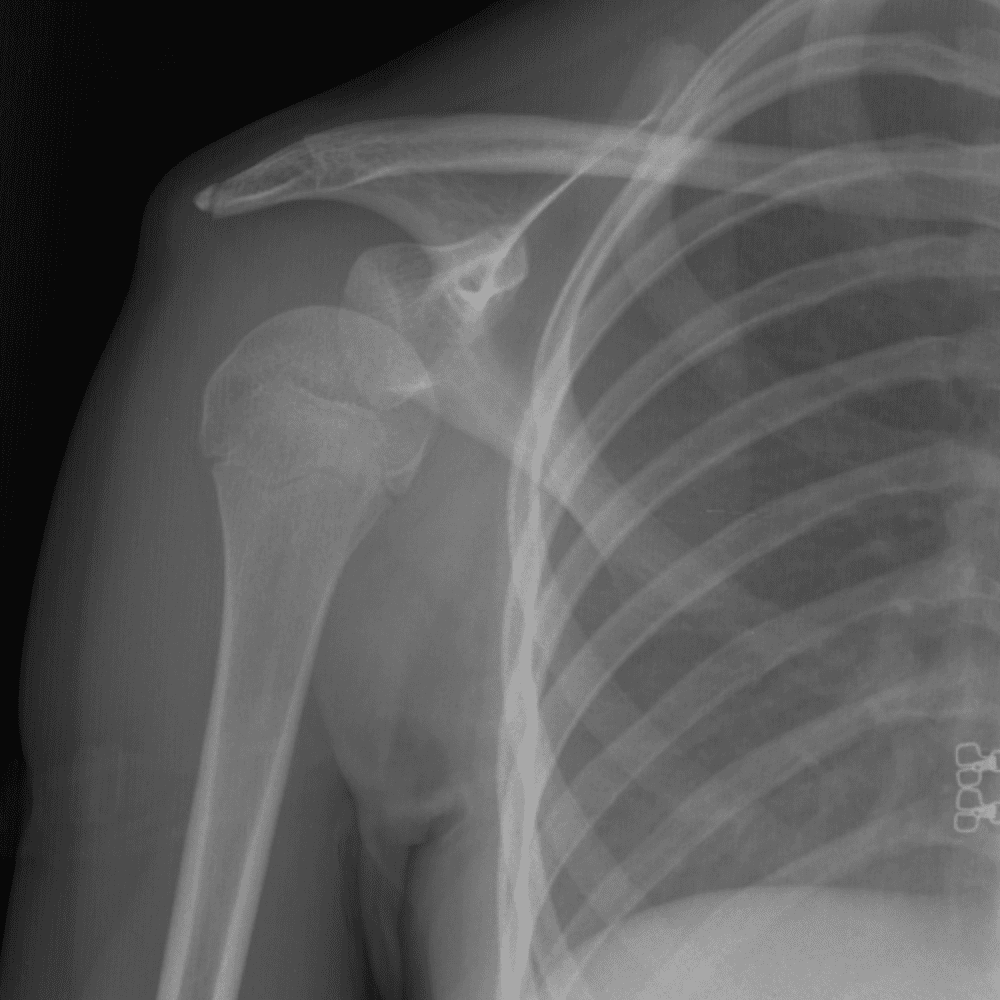

Simuliert den Dienst durch subtile oder schwierige Fälle und einige Normalbefunde.

30 Fälle